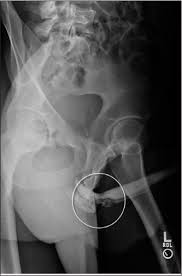

Case 3 Penile Swelling In A 5 Year Old Boy American Academy Of Pediatrics